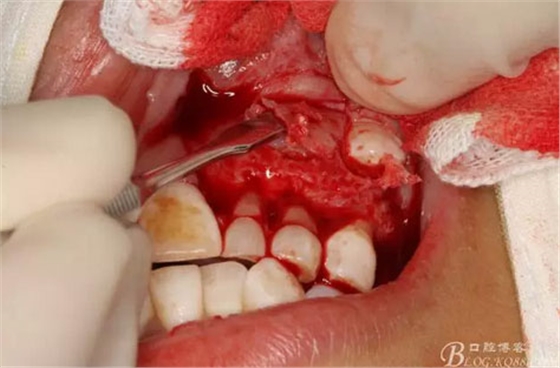

圖17.呼之欲出的巨大牙瘤組織。

圖18.摘除囊腫后遺留的巨大骨腔